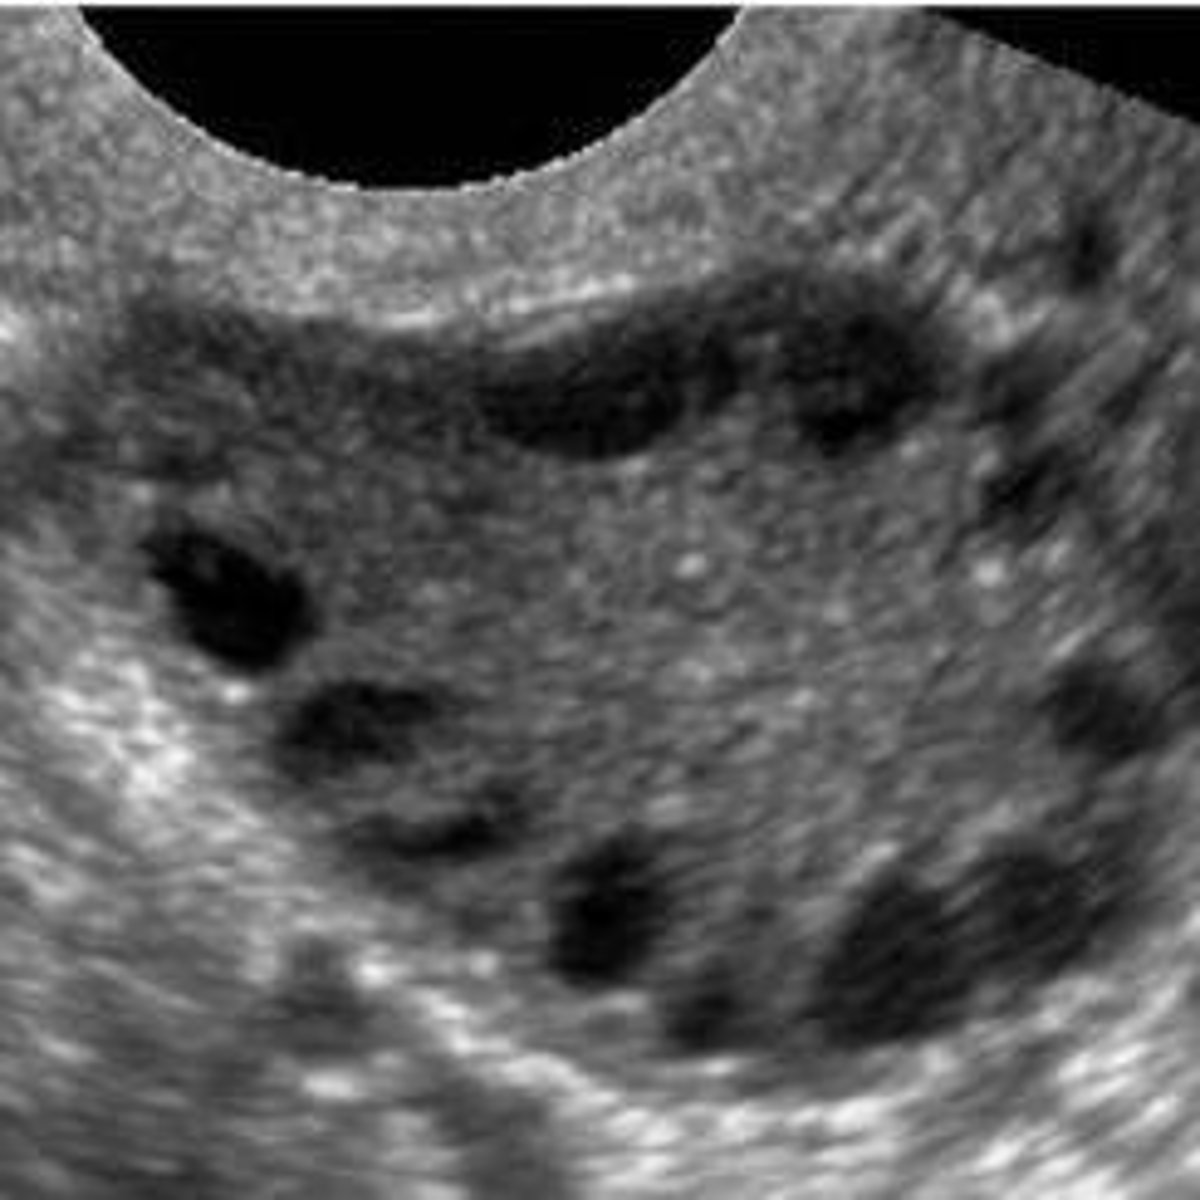

What is the classic ultrasound appearance of ovaries in PCOS?

The 'string of pearls' appearance, defined as 12 or more follicles (2-9 mm) or increased ovarian volume (> 10 mL).